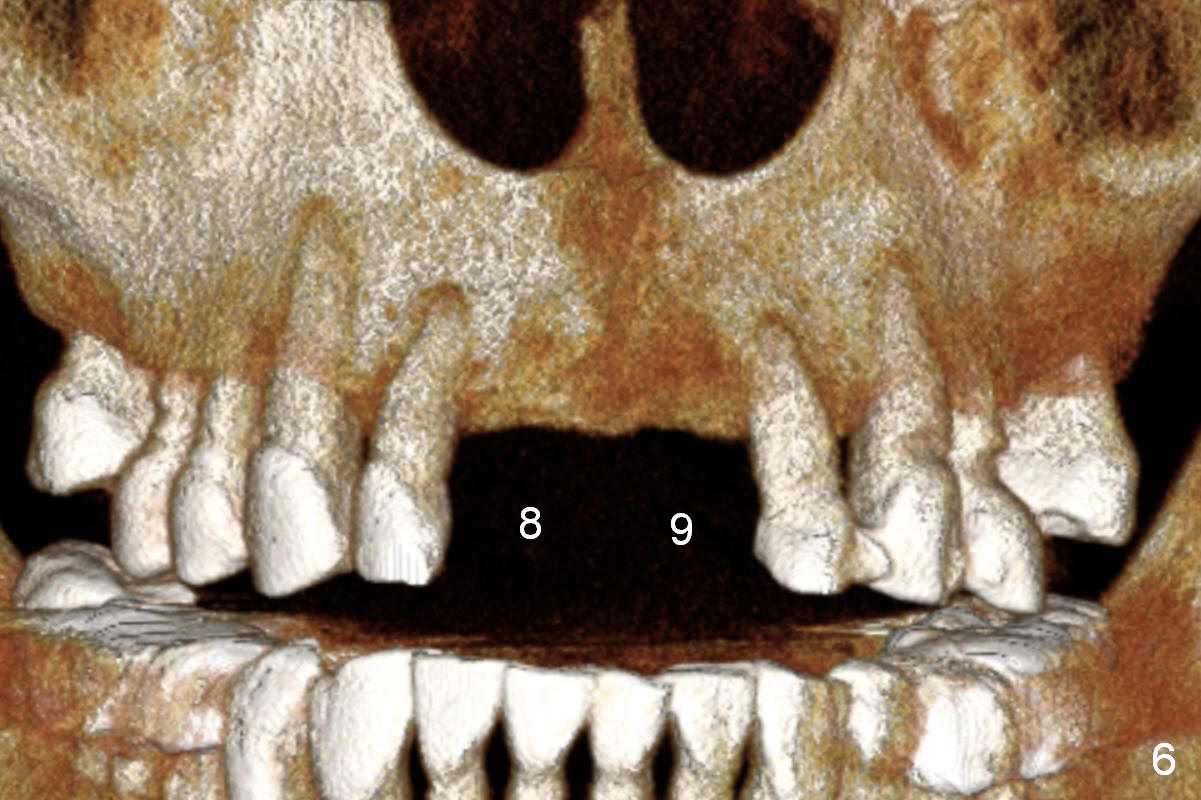

Since previous surgeries have demonstrated dense bone, bone expansion will be not used. Regular drills or reamers will be used for osteotomy. Pay attention to the Incisive Foramen while starting osteotomy (Fig.6,7).

There are two types of implant design for the upper central incisors. The first one is to place implants as large as possible (Fig.1,2), i.e., place the implants in the middle of the alveolar bone, irrespective of the occlusion with the opposing.

The second design is to place relatively smaller implants with the occlusion in mind (Fig.3,4). The starting point for the osteotomy will be as lingual as possible (especially Fig.4). The axis of the implant will be more parallel to the buccal plate. The angles of the angled abutments will be less (Fig.1 vs. 3; Fig.2 vs. 4). The cosmetic result may be better.